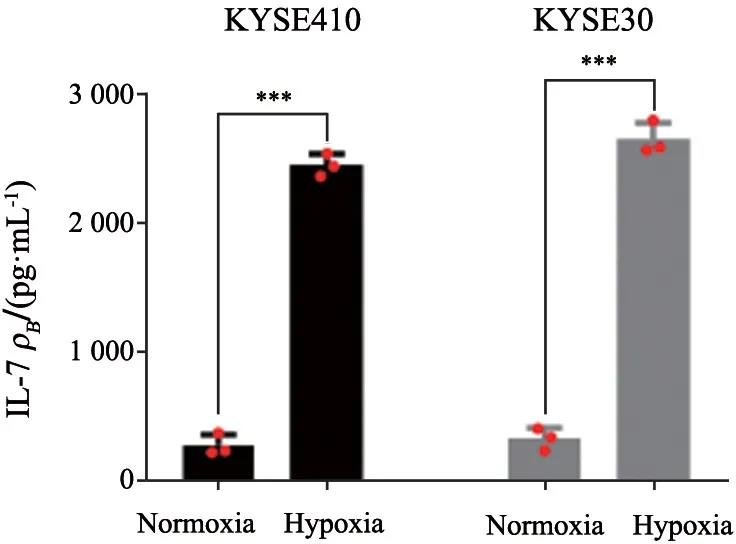

食管癌是常见的消化道肿瘤,中国是食管癌高发国家之一,世界上超过50%的食管癌发生在中国[1-3]。现阶段中国食管癌患者5年生存率为30.3%。食管癌有两种主要的病...